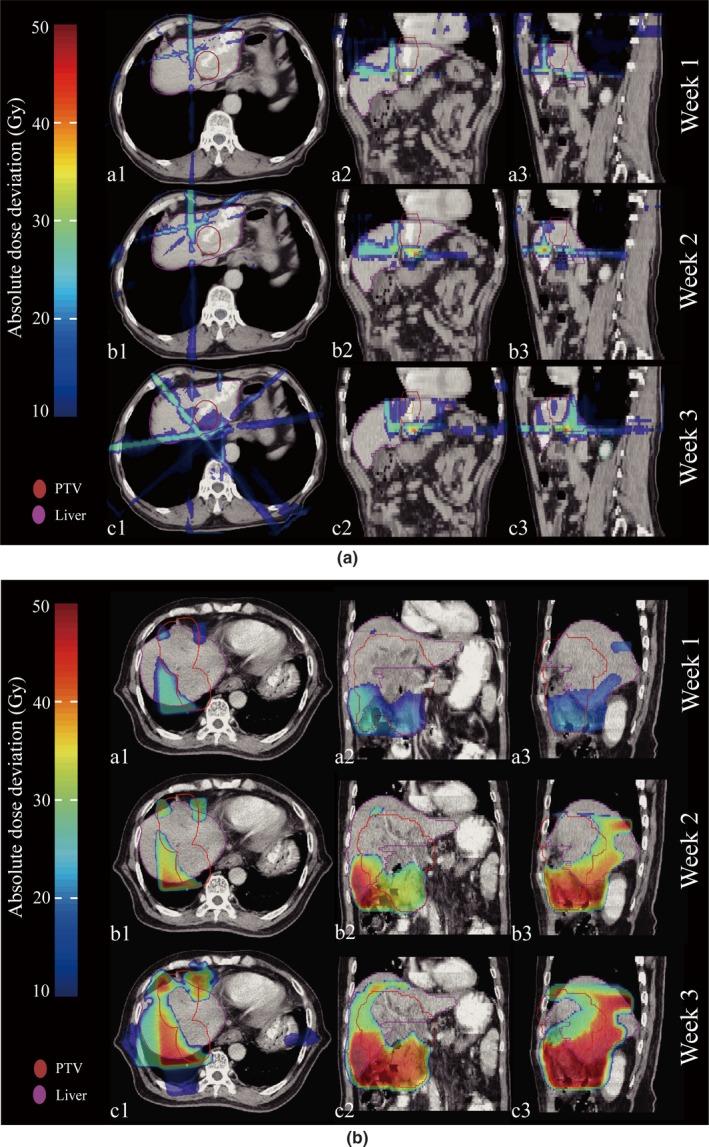

Many patients with technically unresectable or medically inoperable hepatocellular carcinoma (HCC) had hepatic anatomy variations as a result of interfraction deformation during fractionated radiotherapy. We conducted this retrospective study to investigate interfractional normal liver dosimetric consequences via reconstructing weekly dose in HCC patients. Twenty-three patients with HCC received conventional fractionated three-dimensional conformal radiation therapy (3DCRT) were enrolled in this retrospective investigation. Among them, seven patients had been diagnosed of radiation-induced liver disease (RILD) and the other 16 patients had good prognosis after treatment course. The cone-beam CT (CBCT) scans were acquired once weekly for each patient throughout the treatment, deformable image registration (DIR) of planning CT (pCT) and CBCT was performed to acquire modified CBCT (mCBCT), and the structural contours were propagated by the DIR. The same plan was applied to mCBCT to perform dose calculation. Weekly dose distribution was displayed on the pCT dose space and compared using dose difference, target coverage, and dose volume histograms. Statistical analysis was performed to identify the significant dosimetric variations. Among the 23 patients, the three weekly normal liver D increased by 0.2 Gy, 4.2 Gy, and 4.7 Gy, respectively, for patients with RILD, and 1.0 Gy, 2.7 Gy, and 3.1 Gy, respectively, for patients without RILD. Mean dose to the normal liver (D) increased by 0.5 Gy, 2.6 Gy, and 4.0 Gy, respectively, for patients with RILD, and 0.4 Gy, 3.1 Gy, and 3.4 Gy, respectively, for patients without RILD. Regarding patients with RILD, the average values of the third weekly D and D were both over hepatic radiation tolerance, while the values of patients without RILD were below. The dosimetric consequence showed that the liver dose between patients with and without RILD were different relative to the planned dose, and the RILD patients suffered from liver dose over hepatic radiation tolerance. Evaluation of routinely acquired CBCT images during radiation therapy provides biological information on the organs at risk, and dose estimation based on mCBCT could potentially form the basis for personalized response adaptive therapy.

许多技术上无法切除或医学上无法手术的肝细胞癌(HCC)患者在分次放疗期间因分次间变形而出现肝脏解剖结构变异。我们进行了这项回顾性研究,通过重建HCC患者的每周剂量来调查分次间正常肝脏的剂量学后果。23例接受常规分次三维适形放疗(3DCRT)的HCC患者纳入了这项回顾性研究。其中,7例患者被诊断为放射性肝病(RILD),另外16例患者治疗后预后良好。在整个治疗过程中,每周为每位患者进行一次锥束CT(CBCT)扫描,对计划CT(pCT)和CBCT进行可变形图像配准(DIR)以获取修正后的CBCT(mCBCT),并通过DIR传播结构轮廓。将相同的计划应用于mCBCT进行剂量计算。每周剂量分布显示在pCT剂量空间上,并使用剂量差异、靶区覆盖和剂量体积直方图进行比较。进行统计分析以确定显著的剂量学变异。在这23例患者中,有RILD的患者每周三次正常肝脏剂量分别增加0.2 Gy、4.2 Gy和4.7 Gy,无RILD的患者分别增加至1.0 Gy、2.7 Gy和3.1 Gy。有RILD的患者正常肝脏的平均剂量(D)分别增加0.5 Gy、2.6 Gy和4.0 Gy,无RILD的患者分别增加0.4 Gy、3.1 Gy和3.4 Gy。对于有RILD的患者,第三次每周D和D的平均值均超过肝脏放射耐受量,而无RILD的患者的值低于该耐受量。剂量学结果表明,有和无RILD的患者之间的肝脏剂量相对于计划剂量有所不同,且RILD患者的肝脏剂量超过肝脏放射耐受量。放疗期间对常规获取的CBCT图像进行评估可提供有关危及器官的生物学信息,基于mCBCT的剂量估计可能为个性化反应适应性治疗奠定基础。